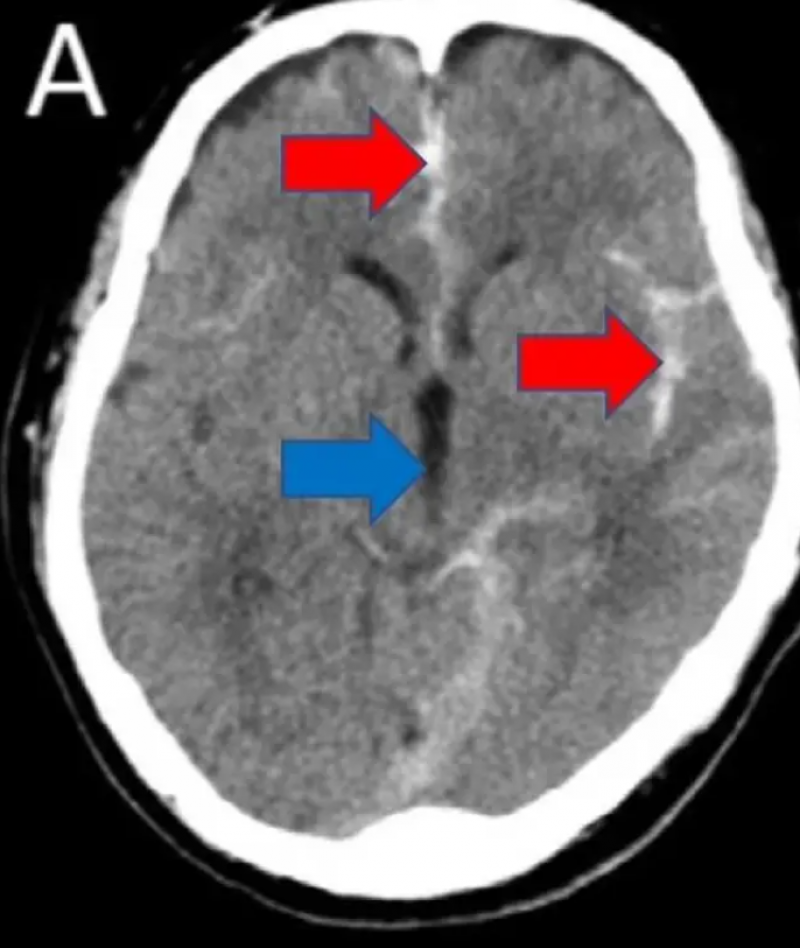

Daaruit bleek dat de man een subarachnoïdale bloeding had opgelopen, of een speciale soort hersenbloeding. Dat gebeurt wanneer je bloeddruk plotseling stijgt en er daarbij meestal een aneurysma in de hersenen knapt. Daardoor stroomt er bloed in de met hersenvocht gevulde delen van je hersenen - en dat is levensbedreigend. Symptomen zijn onder andere erge hoofdpijn, een stijve nek, gevoeligheid aan licht, wazig zicht, slome spraak, vermindering van kracht in één kant van het lichaam en oncontroleerbaar trillen. Ze komen vaak plots op. De onfortuinlijke Japanner, die volgens het rapport regelmatig masturbeerde, kon na twee weken in goede gezondheid het ziekenhuis verlaten.